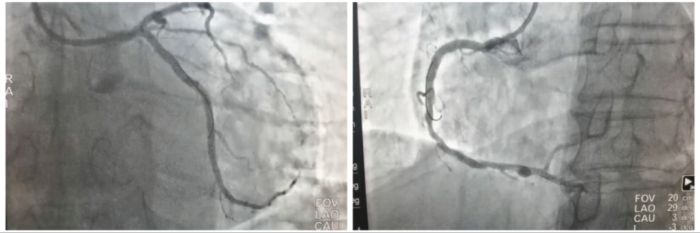

8月15日,心血管内科执行副主任涂涛与行政副主任蒋小菊带领心血管团队在IVUS指导下顺利完成患者右冠脉和回旋支病变的介入治疗。术后再次使用IVUS进行检查,证实支架贴壁良好,无残余狭窄,患者的冠脉血供得到了显著改善。患者对手术过程的体验感及效果给予了充分的肯定和高度评价。

术后患者冠脉血供得到显著改善